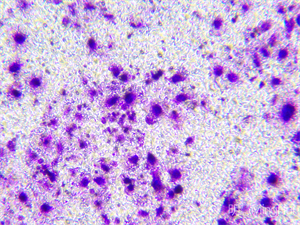

实拍效果图:

MHIL150 倒置显微镜和MHD1200显微镜摄像头的结合:

MHIL150 倒置显微镜可对细胞组织,透明液态组织进行显微观察,也可对培养皿中的培养组织进行动态显微观察,以其稳定的平台设计和优化的光学系统,100X~400X(标准配置)放大倍数,确保了长时间观察过程中细胞的稳定成像。通过MHD1200显微镜摄像头,实时的高清图像被精确捕捉并传输至计算机屏幕,其1200万像素的分辨率让细胞内的细微结构清晰可见,包括细胞膜的波动、细胞骨架的重排。

样品名称:活体细胞

用途:用于观察活体细胞